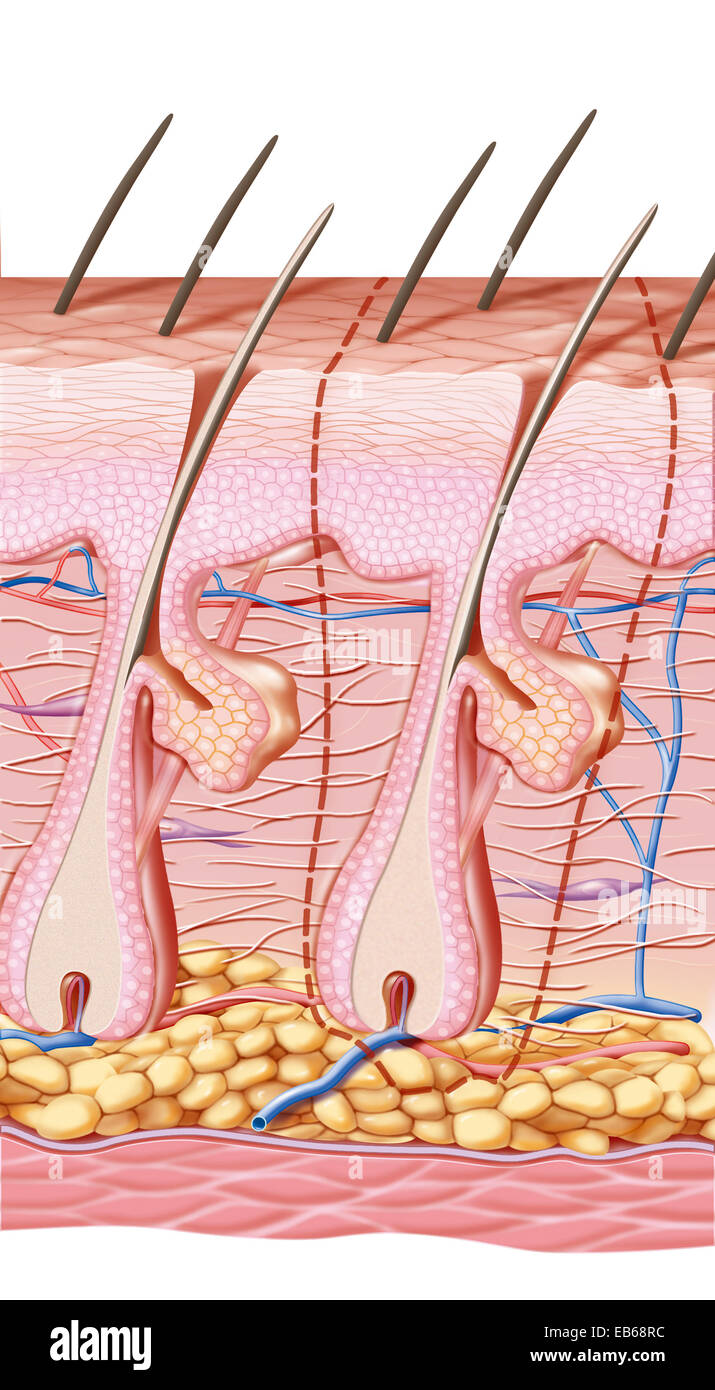

SCAR DRAWING Stock Photohttps://www.alamy.com/image-license-details/?v=1https://www.alamy.com/stock-photo-scar-drawing-75741327.html

SCAR DRAWING Stock Photohttps://www.alamy.com/image-license-details/?v=1https://www.alamy.com/stock-photo-scar-drawing-75741327.htmlRMEB68RB–SCAR DRAWING